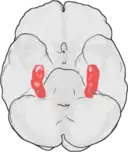

Placeringen af hippocampus i menneskets hjerne.

Mennesket har to hippocampi, en på hver side af hjernen. Hippocampus er en del af det limbiske system og spiller en rolle i menneskets orienteringsevne og hukommelse.